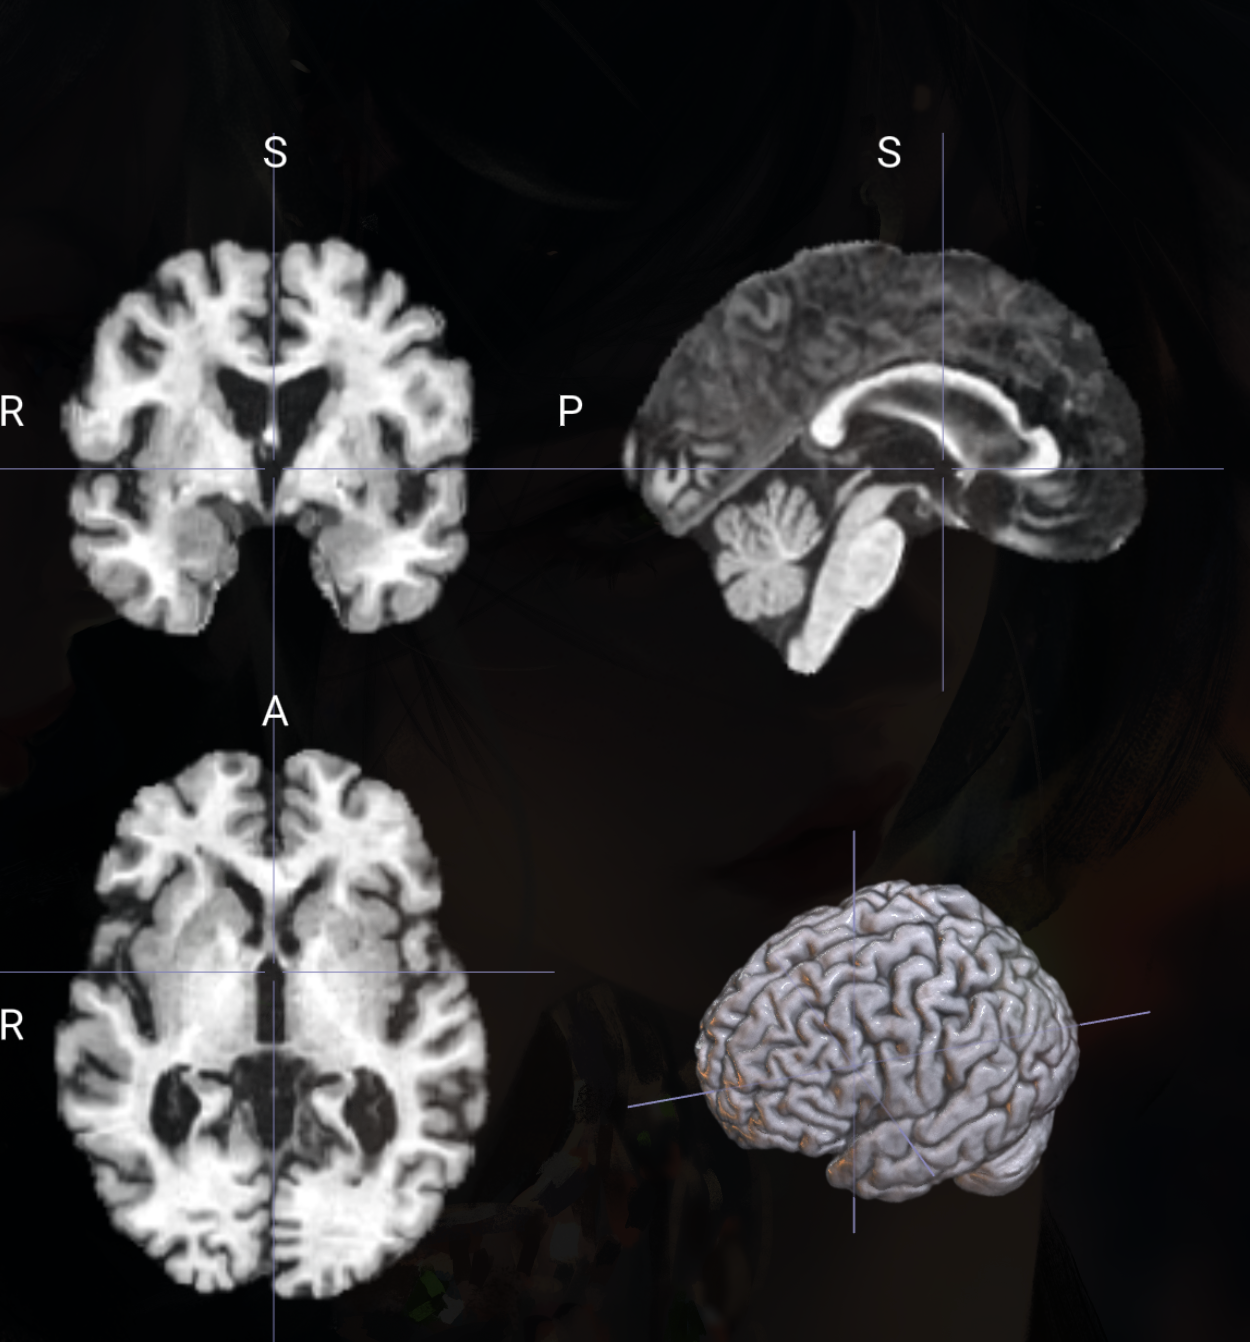

🧠 脑区任务MRI图像预处理

适用于T1、T2、FLAIR模态的脑区提取增强等预处理

MRI数据增强脑子预处理